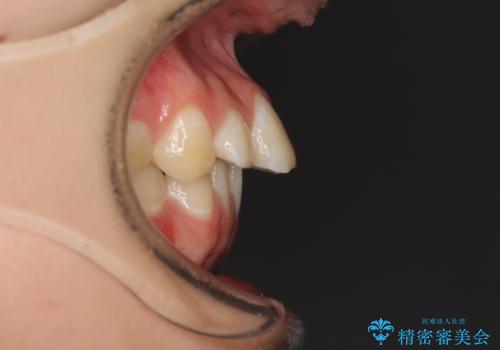

目立つ八重歯を治したい インビザラインによる矯正治療

- 目立つ八重歯を改善したいとのことで来院された患者様です。

奥歯の咬み合わせは左右とも理想的なものでしたが、下顎前歯が1本欠損しているため、上下のバランスを保つことが難しい歯列でした。

唇を閉じたときに上顎前歯が下顎の唇に乗っかる印象があったため、八重歯の後方にある小臼歯を1本抜歯することとしました。

変則的な抜歯となるため、臼歯の咬合が理想的でなくなることが懸念されますが、インビザラインにて矯正治療を行うこととしました。